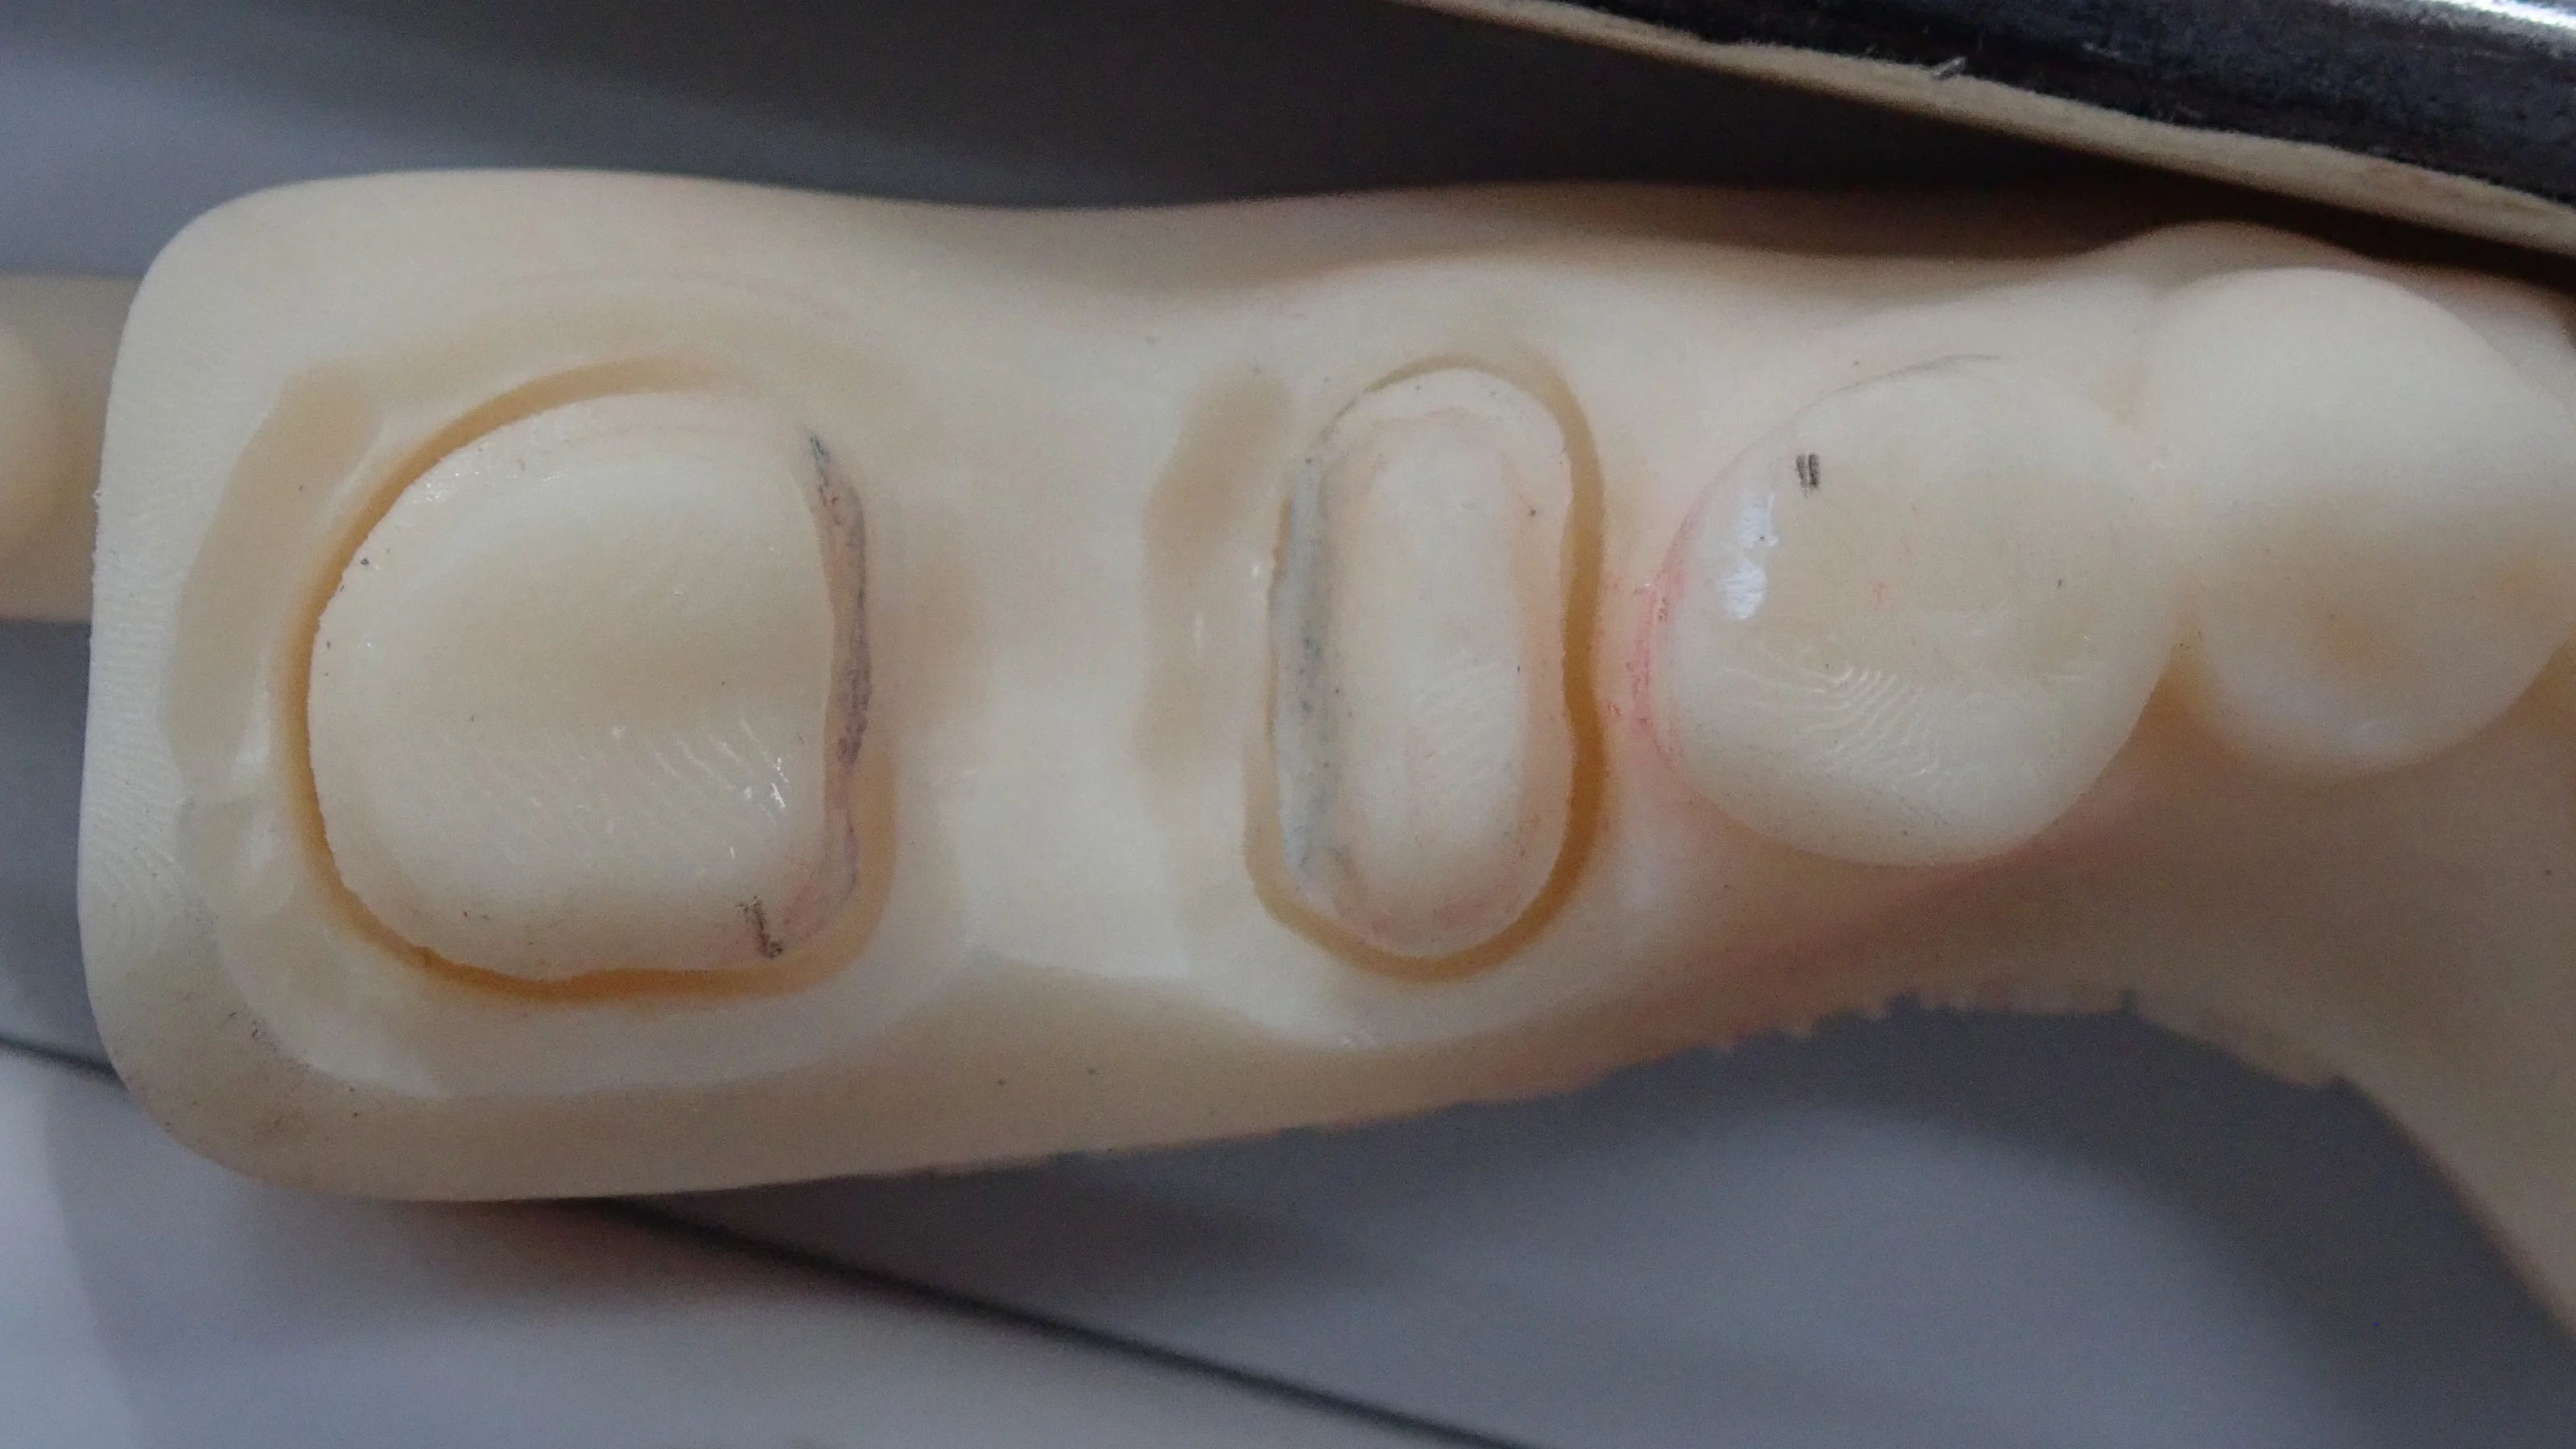

模型がこちらです。

で、セラミックを装着した模型がこちらです。

見た感じ普通に2本の歯っぽく見えるように仕上げてもらいました。

歯がない所謂「ダミー部」については歯間ブラシやブリッジ用のフロスを通せるように若干の隙間を作っています。